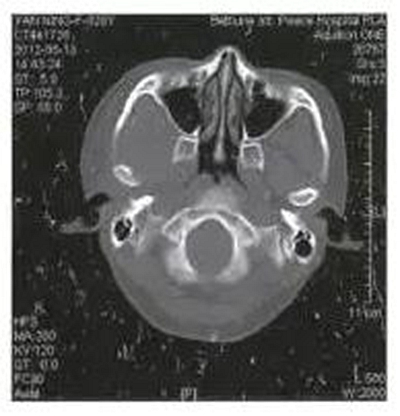

病例1,男,26歲。1月前在當(dāng)?shù)劓?zhèn)醫(yī)院拔除左上頜第三磨牙,術(shù)后3天出現(xiàn)左側(cè)面部腫脹,疼痛,張口受限,張口度約20mm,在當(dāng)?shù)剡M(jìn)行全身抗生素治療,局部未予任何處理,效果不佳。CT示左側(cè)咬肌間隙及顳下間隙腫脹,左側(cè)髁突頸部骨質(zhì)破壞,明顯死骨形成(圖1)。

圖1左側(cè)髁突骨髓炎,死骨形成